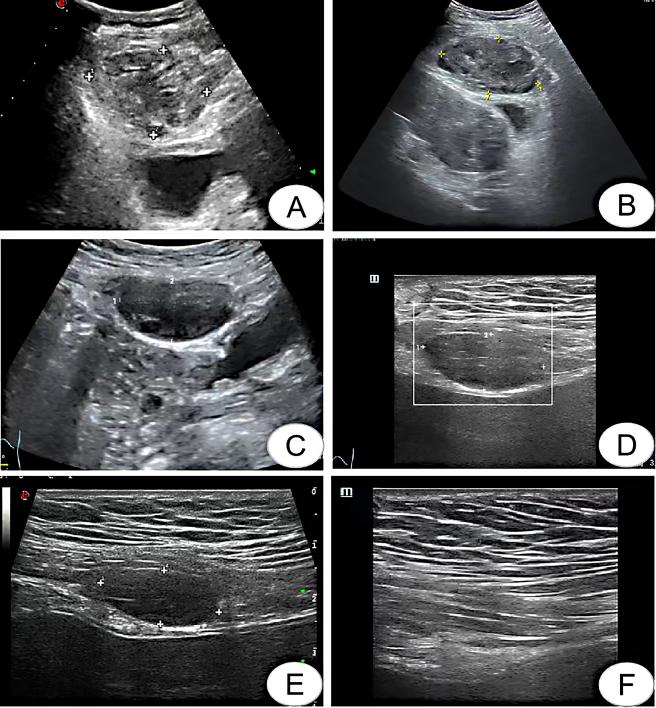

病例2患者34岁,因“停经37周,发现血压升高15 d,头晕2 h”为主诉于2022年6月10日入院。既往有多发性子宫肌瘤病史3年。生育史:0-0-0-0。6月12日因“重度子痫前期”行子宫下段剖宫产术。术中见子宫后壁一枚肌瘤样突起,大小约3 cm×4 cm,予完整剔除,病理证实为子宫平滑肌瘤伴梗死。手术过程顺利,术后予解痉、降压、补充白蛋白、预防感染及补液支持等治疗。剖宫产术后24 h,予低分子肝素针一支皮下注射1次/d预防发生血栓。术后血压波动于118~152/76~95 mmHg。术后第5天出现右下腹压痛,查腹部超声提示子宫前方包块,大小约5.75 cm×4.16 cm×4.12 cm(图 2A),考虑浆膜下肌瘤红色变性可能,不能排除腹直肌鞘血肿,急查血常规及凝血功能正常,即停用低分子肝素针,密切观察产妇症状与体征,术后第9天复查超声提示子宫前方探及一不均质混合回声团,大小约7.07 cm×3.87 cm×5.56 cm,考虑腹直肌鞘血肿(图 2B)。患者无特殊不适,血液检查结果无明显异常,自动离院。出院1个月后随访,超声提示血肿大小约4.92 cm×2.69 cm×2.50 cm(图 2C);3个月后随访,超声提示血肿大小约3.07 cm×1.42 cm×2.73 cm(图 2D);4个月后随访,超声提示血肿大小约2.27 cm×1.00 cm×2.30 cm(图 2E);8个月后随访,超声提示血肿完全吸收。

| A:6月17日超声提示血肿大小;B:6月21日超声提示血肿大小;C:8月1日超声提示血肿大小;D:9月22日超声提示血肿大小;E:10月25日超声提示血肿大小;F:2023年2月28日超声提示血肿消失 图 2 病例2影像检查结果 |